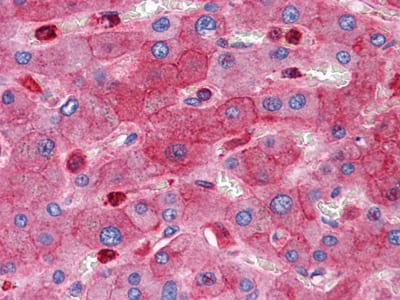

分类: 科研抗体货号: 20357别名: HAP; ASYIP; NSPL2; NSPLII; RTN3-A1应用: IHC反应种属: Human

分类: 科研抗体货号: 20369别名: eN; NT5; CD73应用: IHC反应种属: Human